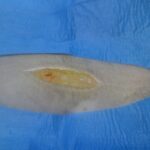

Sorrollatje me rrezik jete

{shikoni me vemendje fotot e syrit dhe veshit}

Ky eshte Ziko. Eshte “mjekuar” disa jave ne nje klinike pastaj ne nje spital. Kur erdhi ne kliniken tone kishte rene mbi 10 kg nga pesha e vet, ishte i pa fuqishem per te ecur,me te vjella dhe ikter. E bardha e syrit ishte bere e verdhe e theksuar dhe veshet nga brenda kishin filluar te zverdheshin Nuk kishte oreks dhe vazhdonte te dobesohej. Pas ekzaminimeve te kryera ne kliniken tone e diagnostikuam me Anaplazma Fagocitosum. I thame pronarit te tij qe do i bejme mjekimin tone dhe pas 3 ditesh do te fillonte ndryshimi. Realisht pas tre ditesh filloi te ndjehej ndryshimi…..Pas perfundimit te kures pronari ndoqi me perpikmeri rekomandimet tona dhe tashme Ziko ushqehet vete, ka shtuar ne peshe, ka fituar gjallerine e humbur dhe ka rifilluar vrapimin te Liqeni me pronarin e tij. Shikoni dy fotot e fundit te Zikos pak para perfundimit te mjekimt.